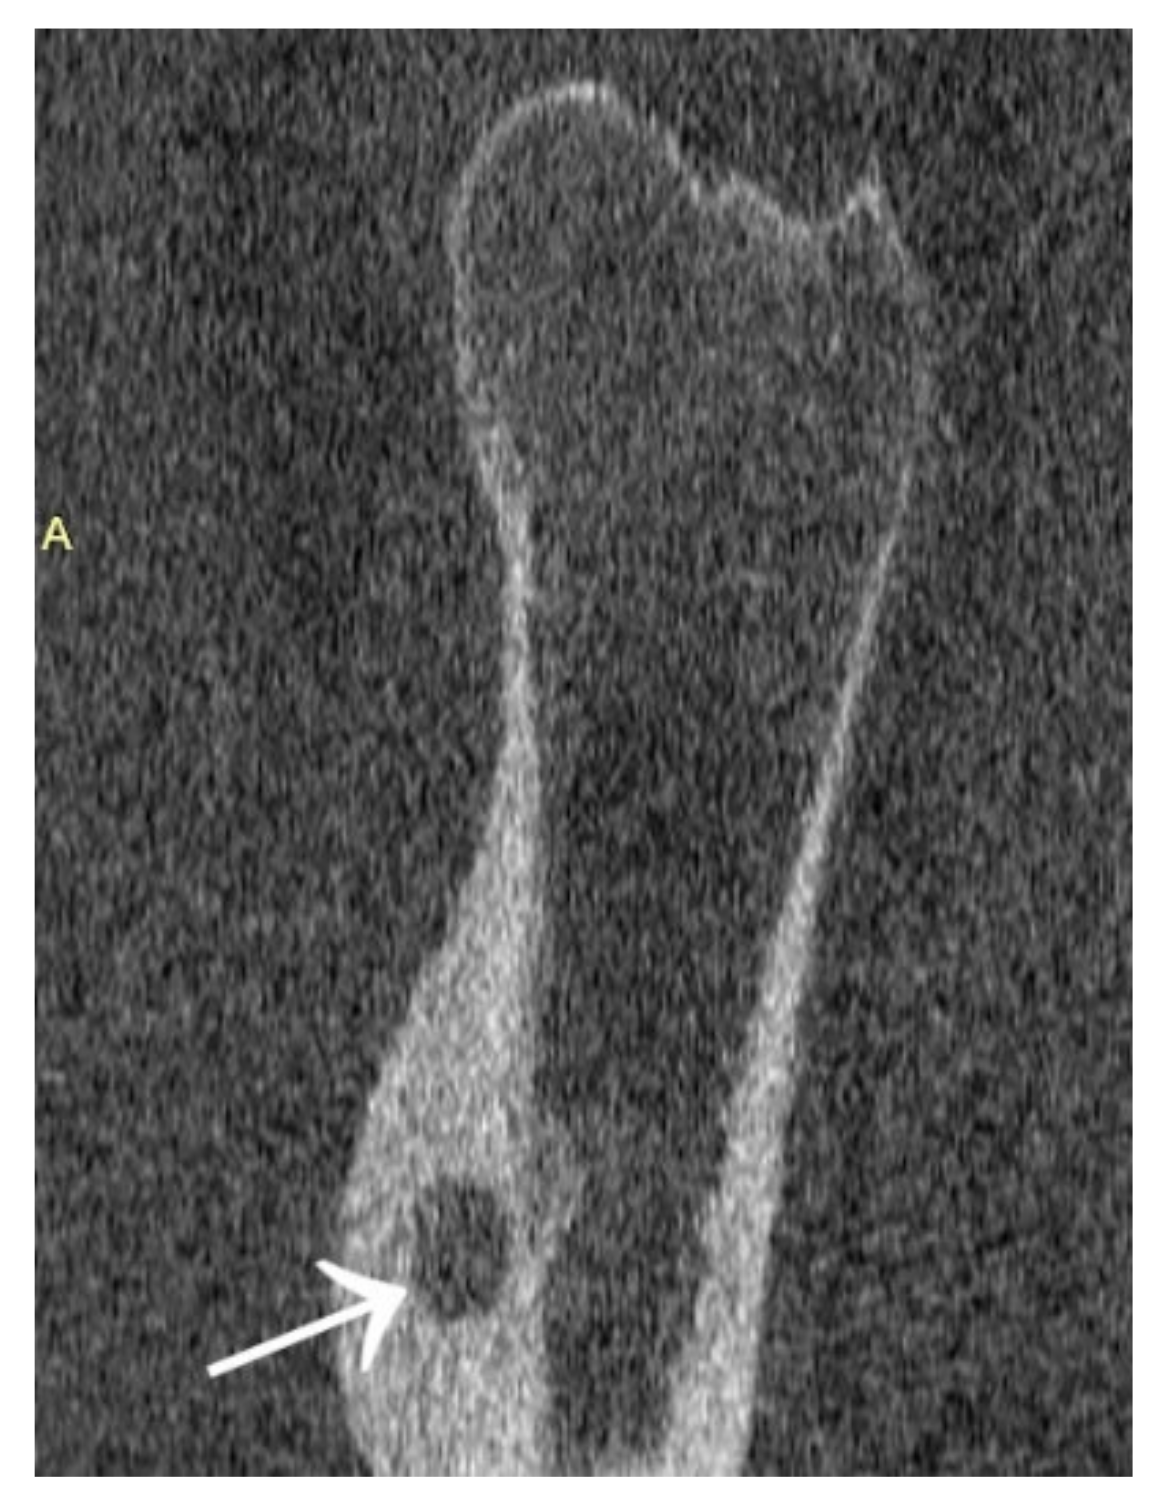

Figure 20.

MRI scans showing a focus of OO (arrows) in the left tibia.